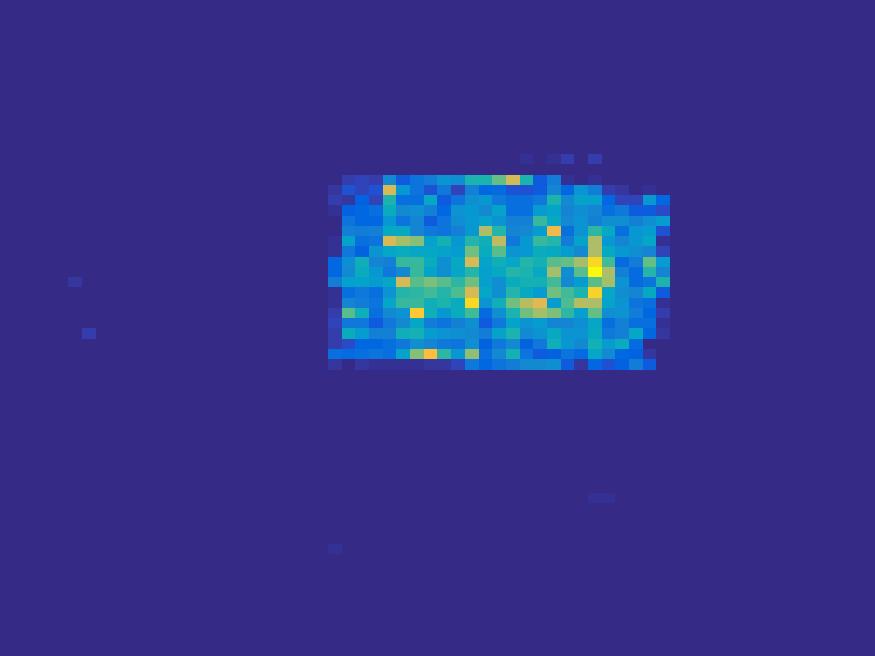

In the tests, projections at two orthogonal angles are simulated for every frame to mimic 2-head camera data collection. The projection angles increase sequentially by along temporal direction. For example, at frame 1, projections are simulated at angle and , and at frame 2, angle and , etc. Finally, white Gaussian noise is added to the projection data. Reconstruction results with different methods are shown in Figure 3. Since the number of projections is very limited for each frame, the traditional FBP and least square methods cannot reconstruct the images satisfactorily, while the proposed method is capable to reconstruct the images effectively. Compared with SEMF model, when the edge of images jump (see frame 21 -frame 31 in Figure 3), the proposed model can better capture the change of the tendency of TAC.

| Frame 1 | Frame 11 | Frame 21 | Frame 31 | Frame 41 | Frame 51 | Frame 61 | Frame 71 | Frame 81 |